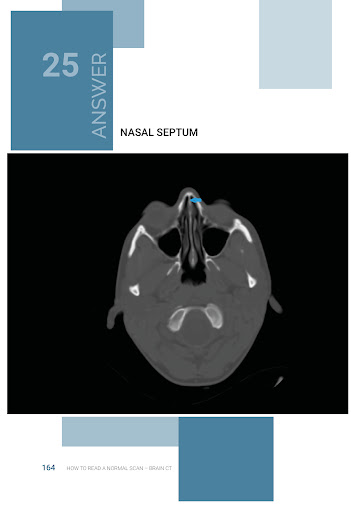

This is an exciting and easy to use Atlas / Quiz of NORMAL Neuroradiology, and attempts to bridge the gap between Anatomy atlases and Radiology atlases. It focuses on the needs of neurology residents and medical students, but anyone who is interested in the radiological anatomy of the brain will find it useful. Using these books as android apps is also reducing production cost , saving printing cost (and trees too in case you like trees). But these same books are also available elsewhere as print versions, but for higher cost.

The objective of the “How to Read a Normal Scan’ series is to familiarize you with NORMAL anatomy as seen on MRI scans and CT scans before memorizing what Hallevorden Spatz or Blah

Blah looks like (sure enough in your Board exam they will want you to identify Blah Blah that no one has seen in 500 doctor years). My hope is, that after reading these books, at the very least you can point out structures on a normal scan and identify exactly what they are. And it is not just about avoiding the embarrassment of ignorance, it is about the sheer satisfaction of knowing what these things are.. If you notice any errors please reach out to me and I will be sure to fix it in the next edition.